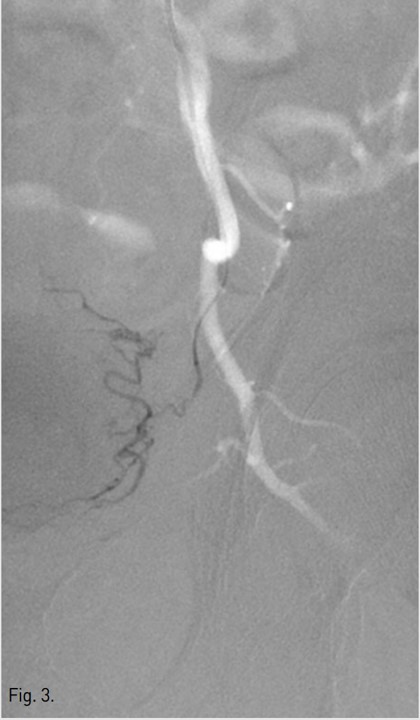

Fig. 4.

Fig. 4. After embolization, left internal iliac angiogram shows no blood flow to the left vesical artery.

우측 총대퇴동맥을 역방향천자하여 5F sheath(Terumo, Tokyo, Japan)를 삽입함. 5F Robert uterine catheter(Cook, Bloomington, USA)를 사용하여 좌측 내장골동맥을 선택한 후 방광에 삽입되어 있는 Foley catheter를 통해 10%로 희석된 조영제 100ml를 방광 내로 주입한 다음 동맥조영술을 시행함(Fig. 1, 2). 좌측 내장골동맥조영술에서 좌측 아래방광동맥이 두드러지게 커져 보여, 좌측 방광동맥을 미세도관(Progreat, Terumo, Tokyo, Japan)과 미세유도철사(GT wire, Terumo, Tokyo, Japan)로 superselection한 다음 gelfoam으로 색전하였음(Fig. 3). 색전술 시행 후 얻은 좌측 내장골동맥조영술에서 더 이상 방광동맥이 보이지 않았음(Fig. 4) 우측 내장골동맥조영술에서는 이상소견 보이지 않아 우측에서는 색전술을 시행하지 않음. 이후 환자는 혈뇨 증상이 호전됨.